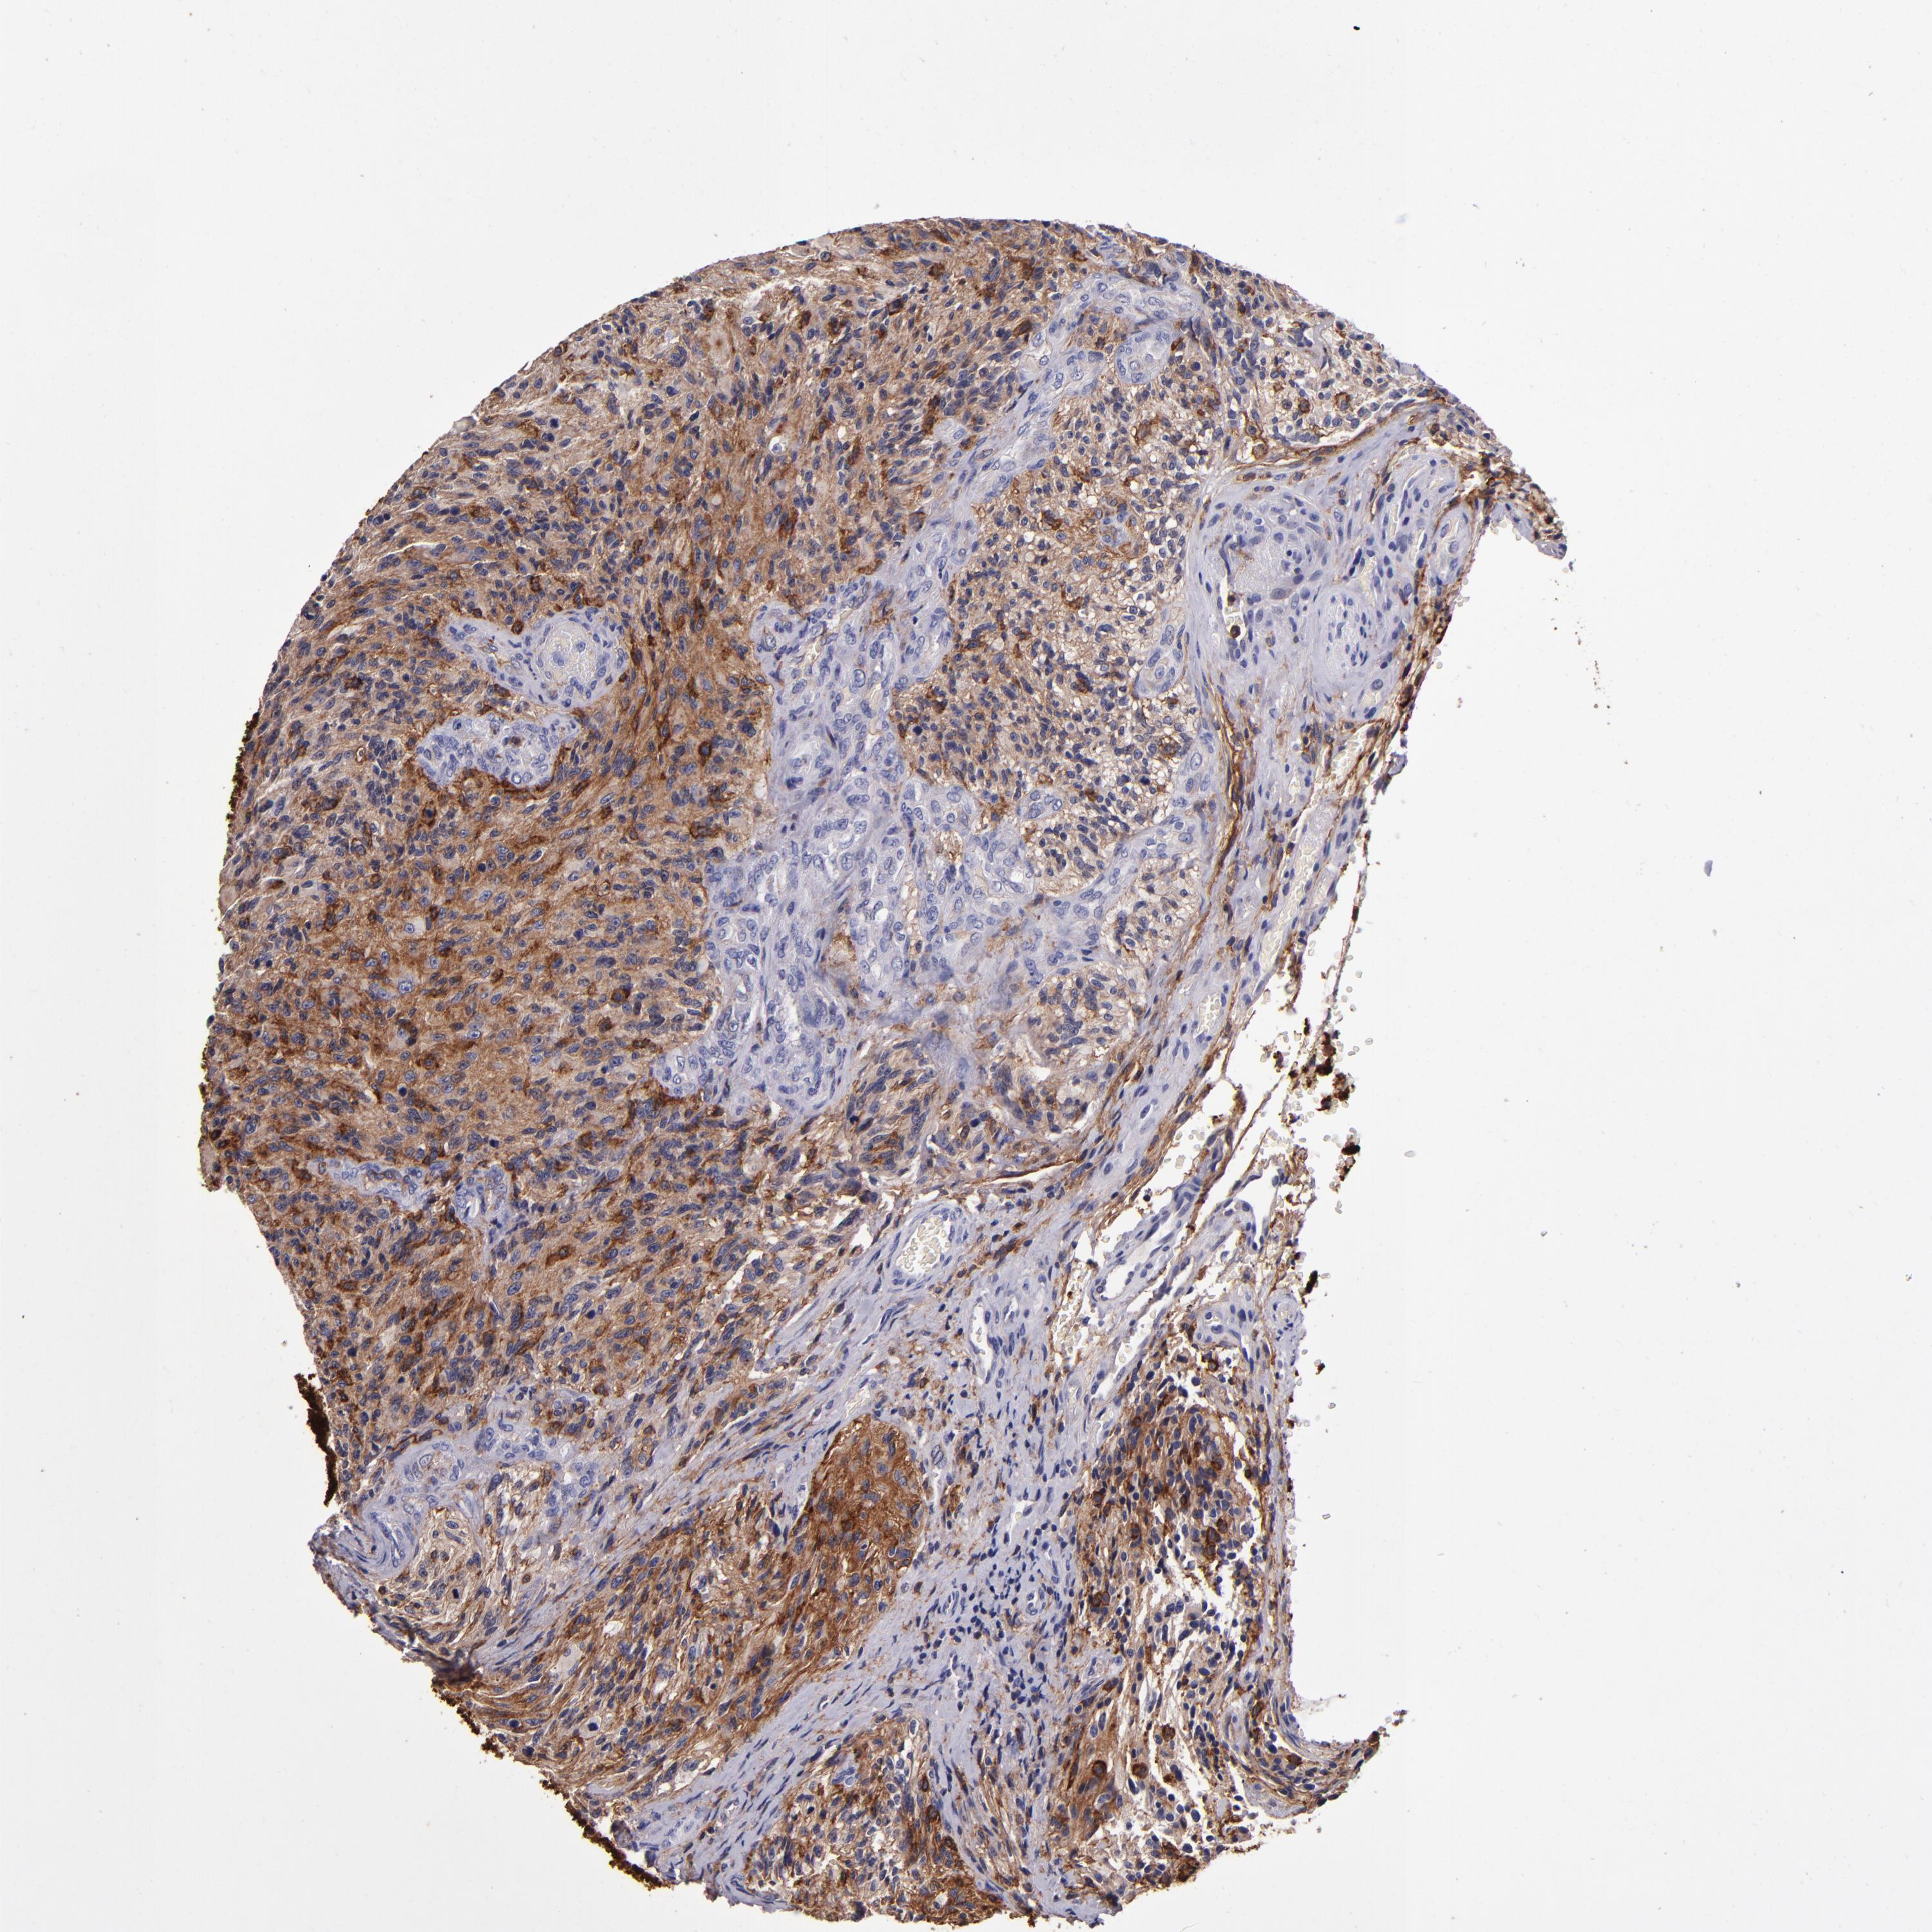

GLIOMA - Protein expressioni

A mouse-over function shows sample information and annotation data. Click on an image to view it in a full screen mode. Samples can be filtered based on level of antibody staining by selecting one or several of the following categories: high, medium, low and not detected. The assay and annotation is described here.

Note that samples used for immunohistochemistry by the Human Protein Atlas do not correspond to samples in the TCGA dataset.

Antibody stainingi

Antibody staining in the annotated cell types in the current human tissue is reported as not detected, low, medium, or high, based on conventional immunohistochemistry profiling in selected tissues. This score is based on the combination of the staining intensity and fraction of stained cells.

Each image is clickable and will lead to virtual microscopy that enables deeper exploration of all samples and also displays staining intensity scores, fraction scores and subcellular localization as well as patient and tissue information for each sample.

Antibody HPA054437

Antibody HPA058511

Antibody CAB002776

Antibody CAB015122

Glioma, malignant, Low grade

Glioma, malignant, High grade

Glioma, malignant, NOS